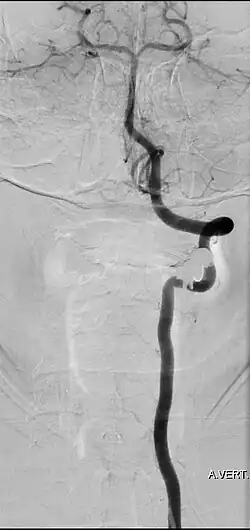

Der Goldstandard zur Visualisierung der Arteria vertebralis ist die digitale Subtraktionsangiographie. Andere bildgebende Verfahren, wie beispielsweise MR-Angiographie und CT-Angiographie, erlauben ebenfalls eine detaillierte Darstellung der Arteria vertebralis.